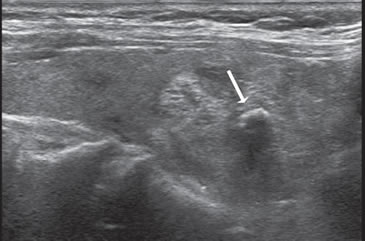

Los nódulos tiroideos se hacen palpables cuando alcanzan aproximadamente 10 mm de tamaño, dependiendo de su localización. Cuando la palpación era la principal manera de identificar nódulos, este diámetro era el límite para realizar una biopsia. Aunque las normas de la Asociación Americana de Endocrinólogos Clínicos (AACE) y la Asociación Americana de Tiroides (ATA) continúan usando 10 a 15 mm como el umbral práctico9,10 para seleccionar nódulos que necesitan de una PAAF, se ha demostrado que el tamaño no es un buen indicador para predecir malignidad. Son varios los trabajos que muestran que la prevalencia de cáncer es similar en nódulos mayores o menores de 10 mm11. La Sociedad de Radiólogos en Ultrasonido recientemente llegó al consenso de que, más que fijar un umbral de tamaño, debe usarse el aspecto ecográfico del nódulo como criterio de selección, tanto en el nódulo solitario como en la glándula multinodular4. En nódulos mayores de 10 mm no habría una diferencia significativa en el porcentaje de malignidad, aunque hay una tendencia que indicaría que la tasa de malignidad es más alta en nódulos mayores de 30-40 mm. El cáncer papilar menor de 10 mm se ha definido como microcarcinoma (Figura 1) y su frecuencia ha aumentado gradualmente en los últimos años12. Persiste el debate si este aumento es real o simplemente se debe al uso masivo de la ecografía cervical y la PAAF guiada por ecografía, lo que permite identificarlos precozmente. La presencia de múltiples nódulos no disminuye la probabilidad de cáncer tiroideo por paciente y el nódulo dominante por mayor tamaño no es necesariamente el que contiene el cáncer, ya que en aproximadamente un 30% el cáncer está en el nódulo no dominante4. Independiente del tamaño los nódulos casi completamente quísticos, sin otras características sospechosas, probablemente no requieren de biopsia.

Figura 1. Microcarcinoma de 8 mm.